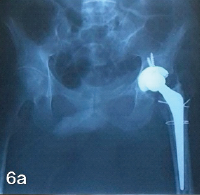

Patient pre-anesthetic evaluation workup was done and posted for surgery. The patient was placed supine on a fracture table, after standard painting and draping, and slight traction was applied. Moreover, closed reduction of the fracture was attempted and achieved under C-arm guidance. A small lateral incision was made proximal to the greater trochanter. An entry point was made at the tip of the greater trochanter under image guidance, and a guidewire was passed through the proximal femur into the shaft. Reaming was done over the guidewire sequentially. A long proximal femoral nail (PFN) (length: 28 cm, diameter: 9 mm) was inserted over the guidewire. Fracture alignment was confirmed under C-arm. 8 mm and 6 mm proximal locking screws were inserted through the jig. Distal locking was done using the freehand technique under C-Arm. Final fluoroscopy confirmed satisfactory fracture reduction, implant position, and screw placement. The wound was irrigated with saline, and hemostasis was ensured. Wound closure was done in layers. A sterile dressing was applied. The post-operative patient was allowed toe-touch with a Zimmer walking frame. Clinical and radiographic follow-up showed no displacement and consolidation after 8 weeks, and hence, full weight-bearing was started as tolerated. The patient was followed up after 5 months, and her physical status was almost comparable to the pre-operative level without any complications (Fig. 3, 4, 5, 6).

Figure 6: Full weight bearing after 5 months.